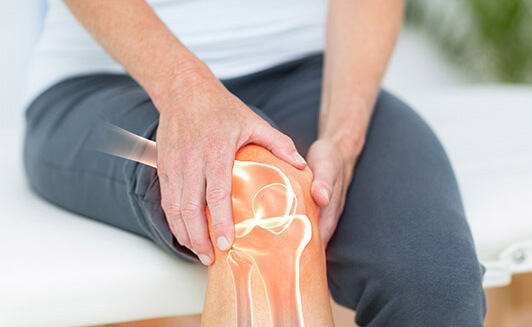

무릎 관절염 원인

무릎 관절염은 여러가지 원인에 의해 발생할 수 있습니다. 가장 일반적인 원인은 연령과 함께 발생하는 자연적인 연골 손상이며, 무릎 관절 과부하, 외상, 근육과 연조직의 약화, 대사성 질환, 유전적 요소 등이 원인이 될 수 있습니다.

1. 연령: 연령이 들어갈수록 무릎 관절의 연골이 더 얇아지고 마모되는 것은 자연스러운 일입니다. 이로 인해 노화성 관절염(오스테오아르트리티스)이 발생할 수 있습니다.